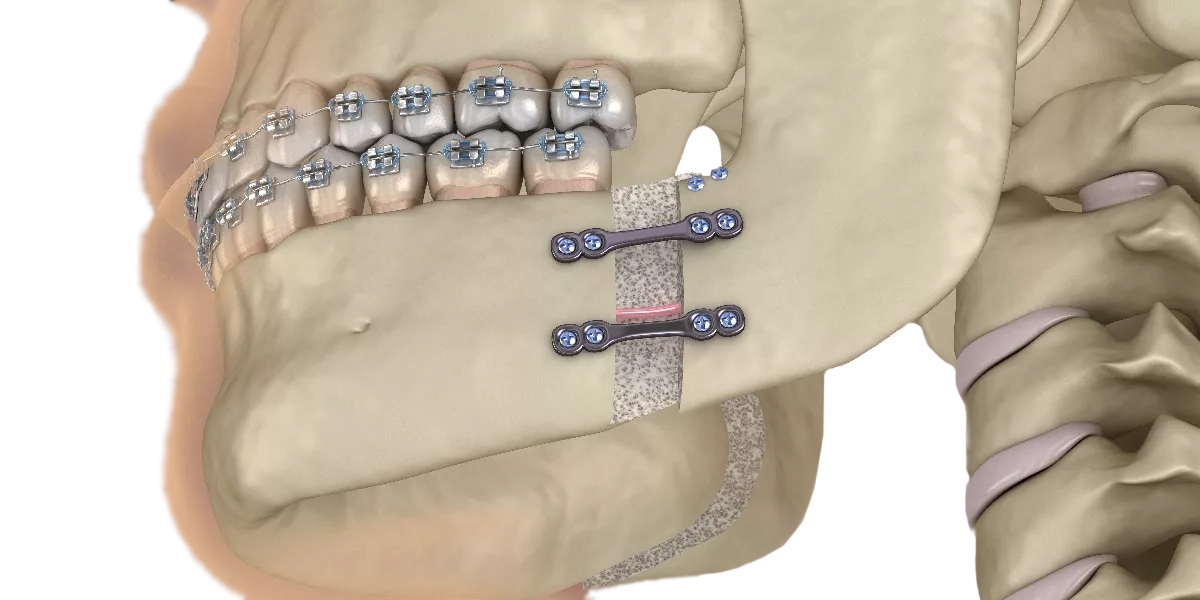

Distraction osteogenesis (DO) is a modern technique used to correct certain deformities and defects of the jaw and skull. Although first introduced in 1903, the method was significantly advanced in the 1950s by Russian orthopedic surgeon Dr. Gabriel Ilizarov, who refined the process for use in limb deformities. The use of distraction osteogenesis in oral and facial treatments began in 1990 and has since evolved into a safe and reliable solution for jaw reconstruction and enhancement.

The term “distraction osteogenesis” means slowly separating two bone segments so new bone can grow to fill the gap. This technique is particularly useful in correcting jaw deficiencies and preparing the bone for dental implants.